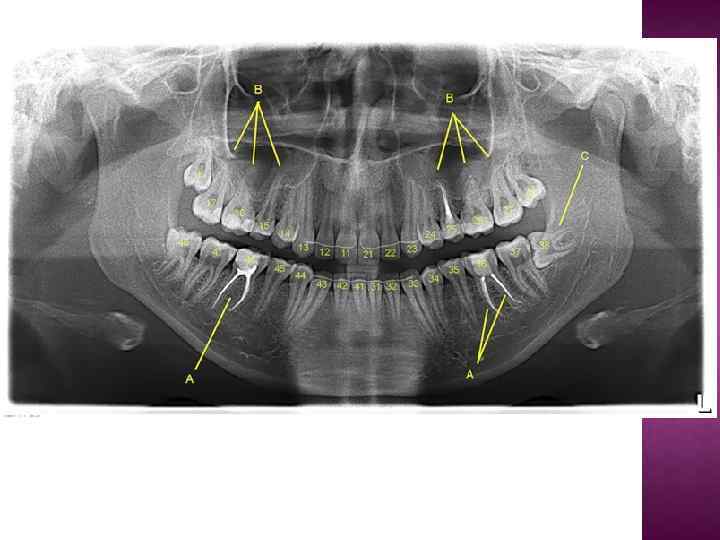

Большинство стоматологических материалов изготавливаются рентгеноконтрастными. Делается это для того, чтобы можно было контролировать объем и расположение этого материала на рентгеновских снимках. Например, пломбировочные материалы для корневых каналов на снимке обозначены буквой А. Ортопантомография дает хорошее представление о расположении зубов мудрости (на снимке буква С). Даже прицельные снимки не дают полной картины о строении и локализации восьмерок. Поэтому без проведения ОПТГ я крайне не рекомендую браться за удаление или лечение "мудрых" зубов.

Проникновение корней зубов в верхнечелюстную пазуху (буква B на снимке). На самом деле, корни зубов ооочень редко проникают в верхнечелюстной синус. Чаще всего они огибают его по краям таким образом, что дно пазухи находится между корней зубов.